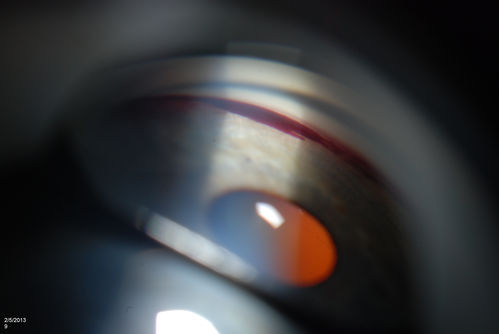

Gonioscopy, Blood in the Anterior Chamber from Hyphema

Patient comes in with blunt trauma to the right eye due to a BB gun incident. Patient was present with a hyphema at 8-o'clock about 1mm thick. Gonioscopy photos were then taken to show blood from the hyphema entered into the anterior chamber. Patient had no angle recession in the right eye.